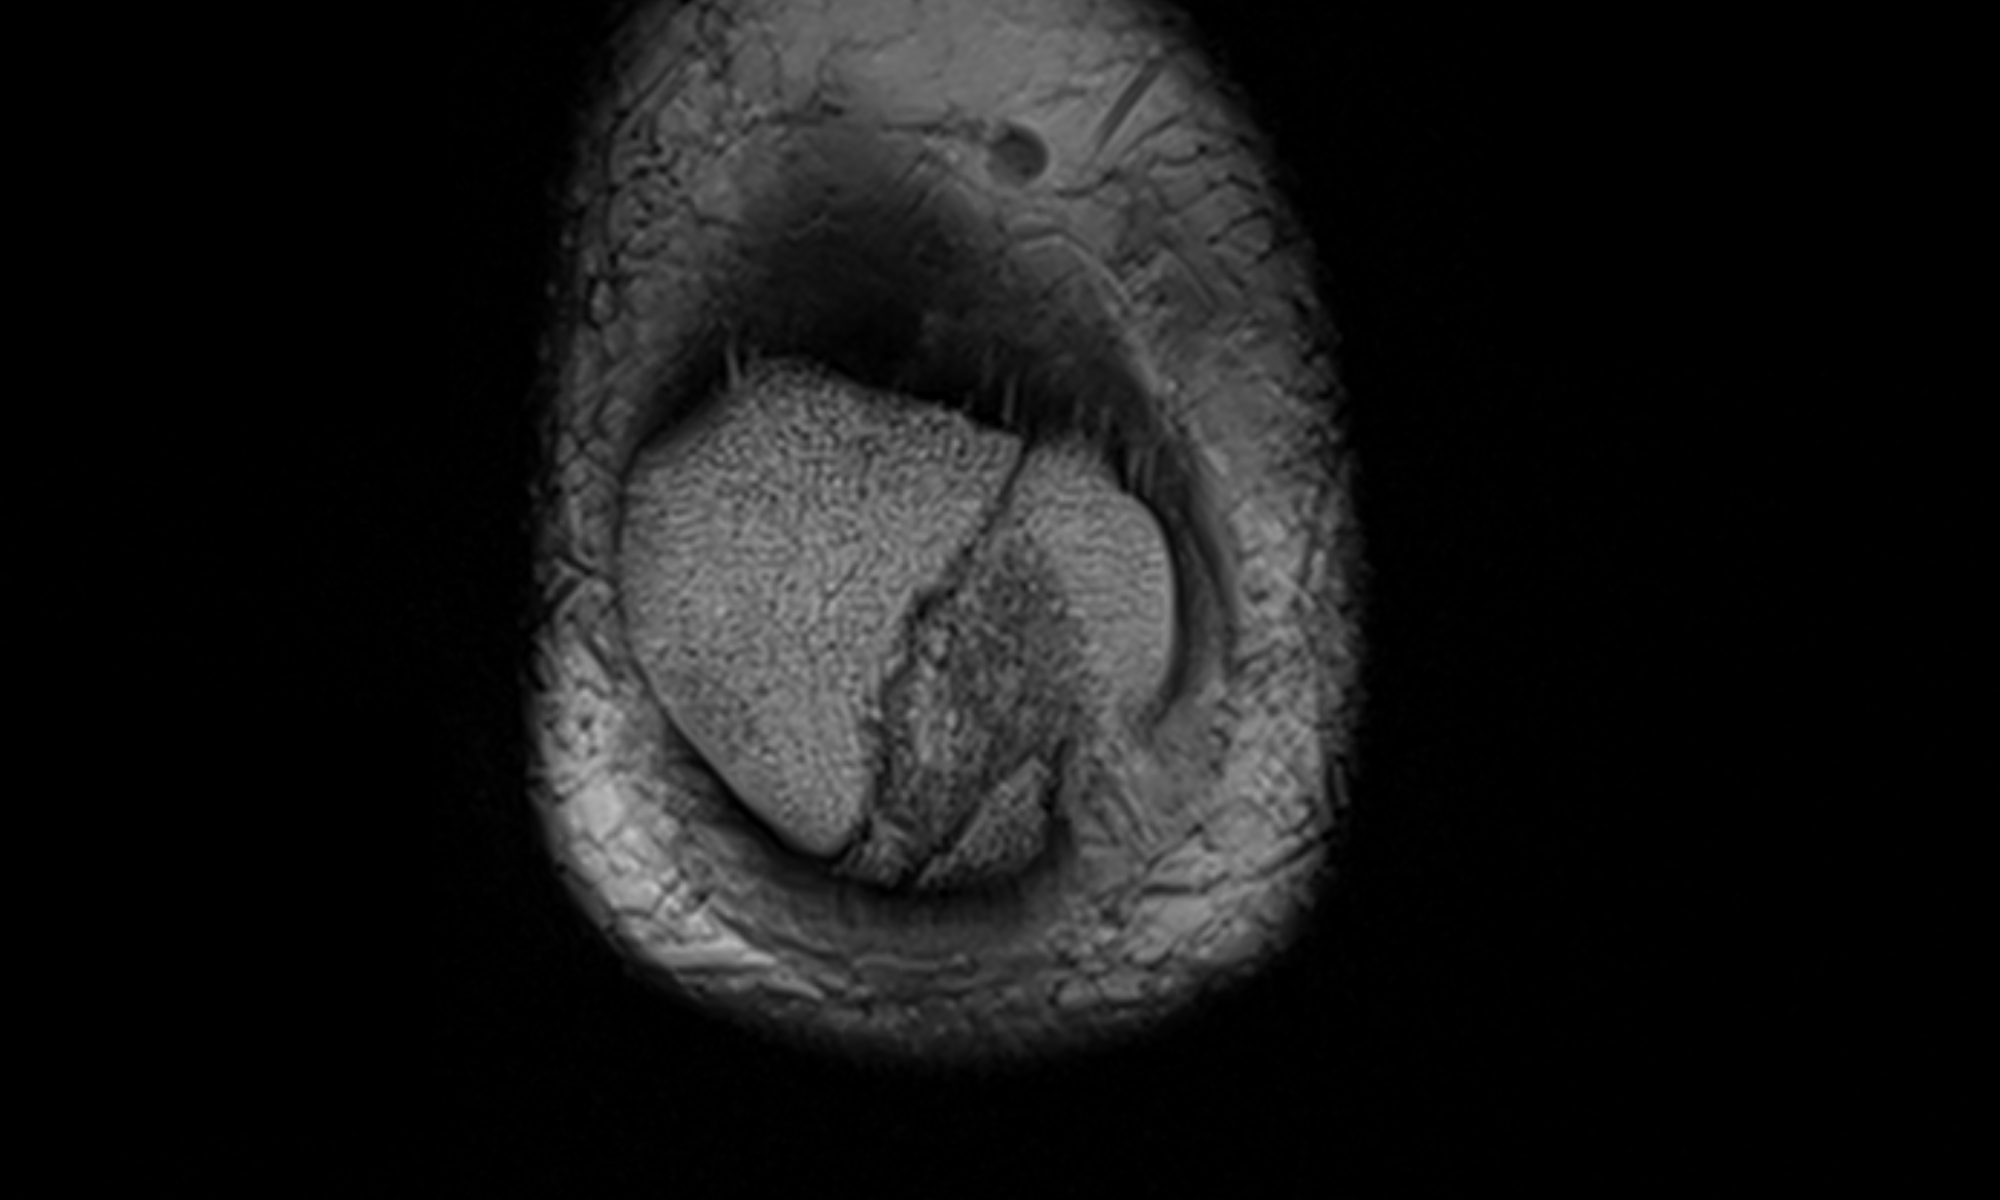

関節穿刺にて血腫を確認後、MRIで膝蓋骨骨折を確認。縦方向に亀裂が入り2分割。その他の関節内骨折は認めず。